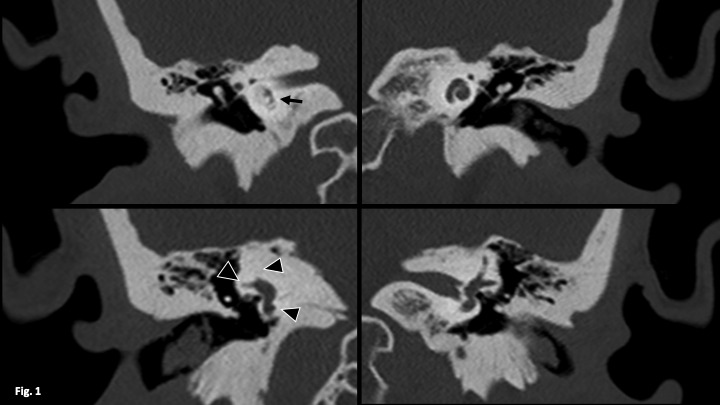

Labyrinthitis ossificans is a pathology consisting of calcification of the membranous labyrinth resulting in profound sensory deafness. It is usually due to an acute inflammatory process that progresses to ossification of the labyrinth. The clinical manifestations are irreversible hearing loss, dizziness and vomiting. It is diagnosed by computed tomography (CT) and magnetic resonance imaging (MRI). It is important to make the correct diagnosis before cochlear implantation, as ossification of the labyrinth can hinder or prevent the implantation of electrodes.